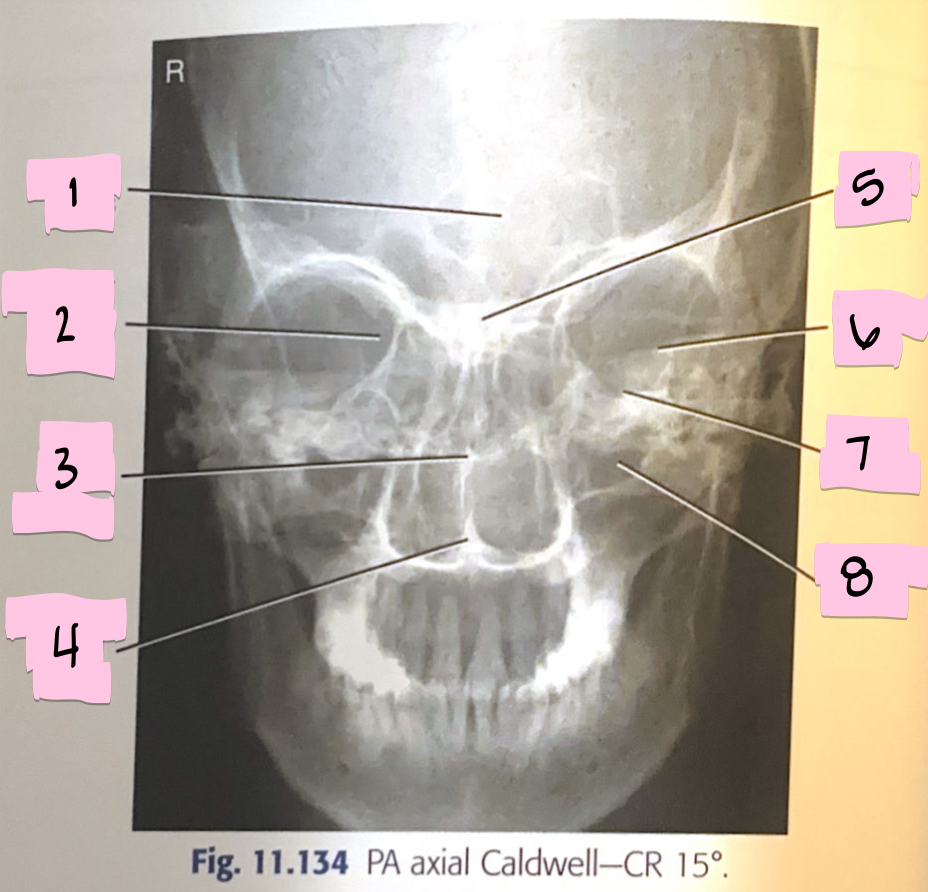

What is 1 pointing to?

Frontal sinus

What is 2 pointing to?

Superior orbital fissure

What is 3 pointing to?

Bony nasal septum

What is 4 pointing to?

Anterior nasal spine

What is 5 pointing to?

Crista galli

What is 6 pointing to?

Petrous ridge

What is 7 pointing to?

Floor of orbit

What is 8 pointing to?

Maxillary sinus